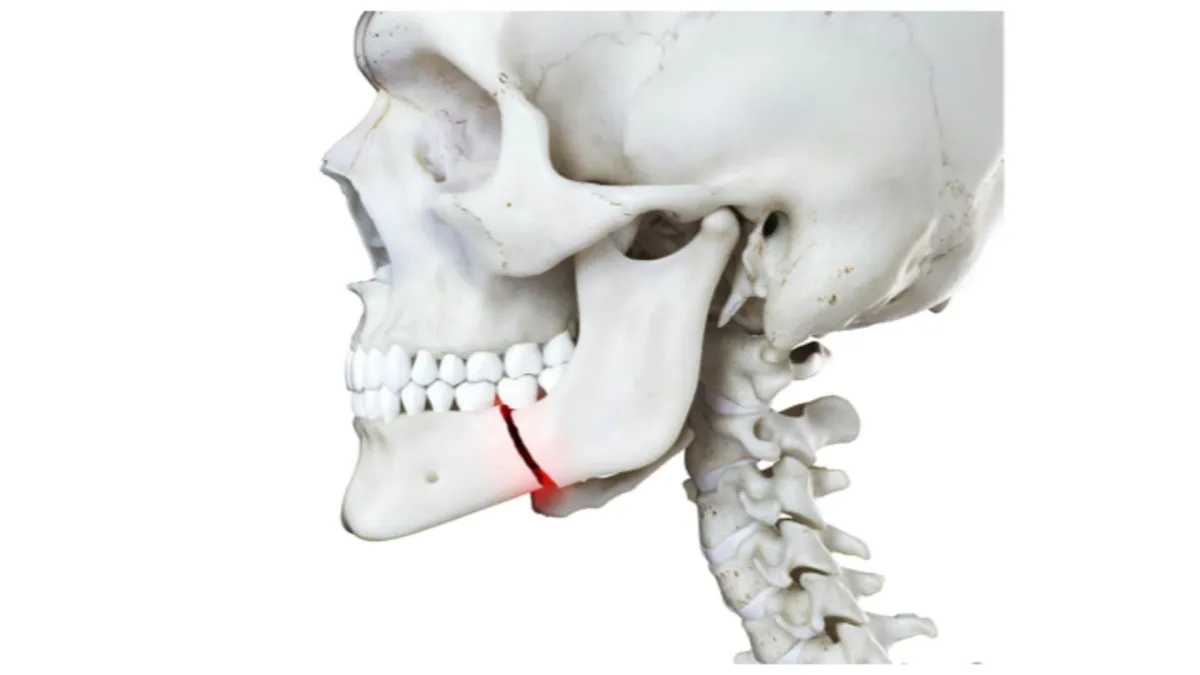

#9 - Injured Your Jaw

A broken jaw is no fun. Basically, there’s nothing you can do for this other than take some over the counter painkillers and put some ice on it until you can get to the ER. You will likely need a maxillofacial surgeon for this and an surgery as soon as possible.